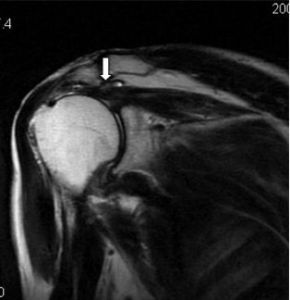

1.X線檢查對肩峰形態的判斷及肩關節骨性結構的改變有幫助。部分肩袖損傷患者肩峰前外側緣及大結節處有明顯骨質增生。2.磁共振(MRI)檢查可幫助確定肌腱損傷的損傷部位和嚴重程度,尤其是磁共振造影檢查(MRA)可以清晰的顯示肩袖的部分撕裂,對診斷具有較高的價值。診斷